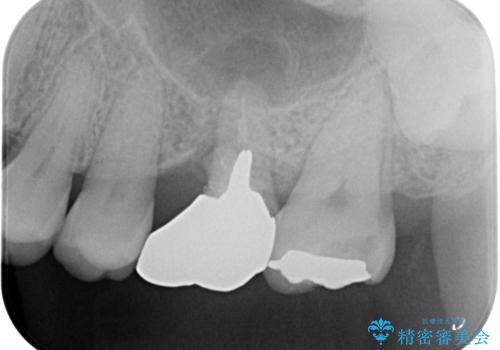

- 左上の奥歯を何とか保存していた患者様です。

今回、残していた歯根から歯茎が大きく腫れ、長期的な予後を期待できないことを考慮し、抜歯してブリッジでの治療を行いました。

- 左上567:仮歯11,000円×3本、ジルコニアクラウン(スタンダード):121,000円×3本 合計396,000円費用は治療当時の料金となります